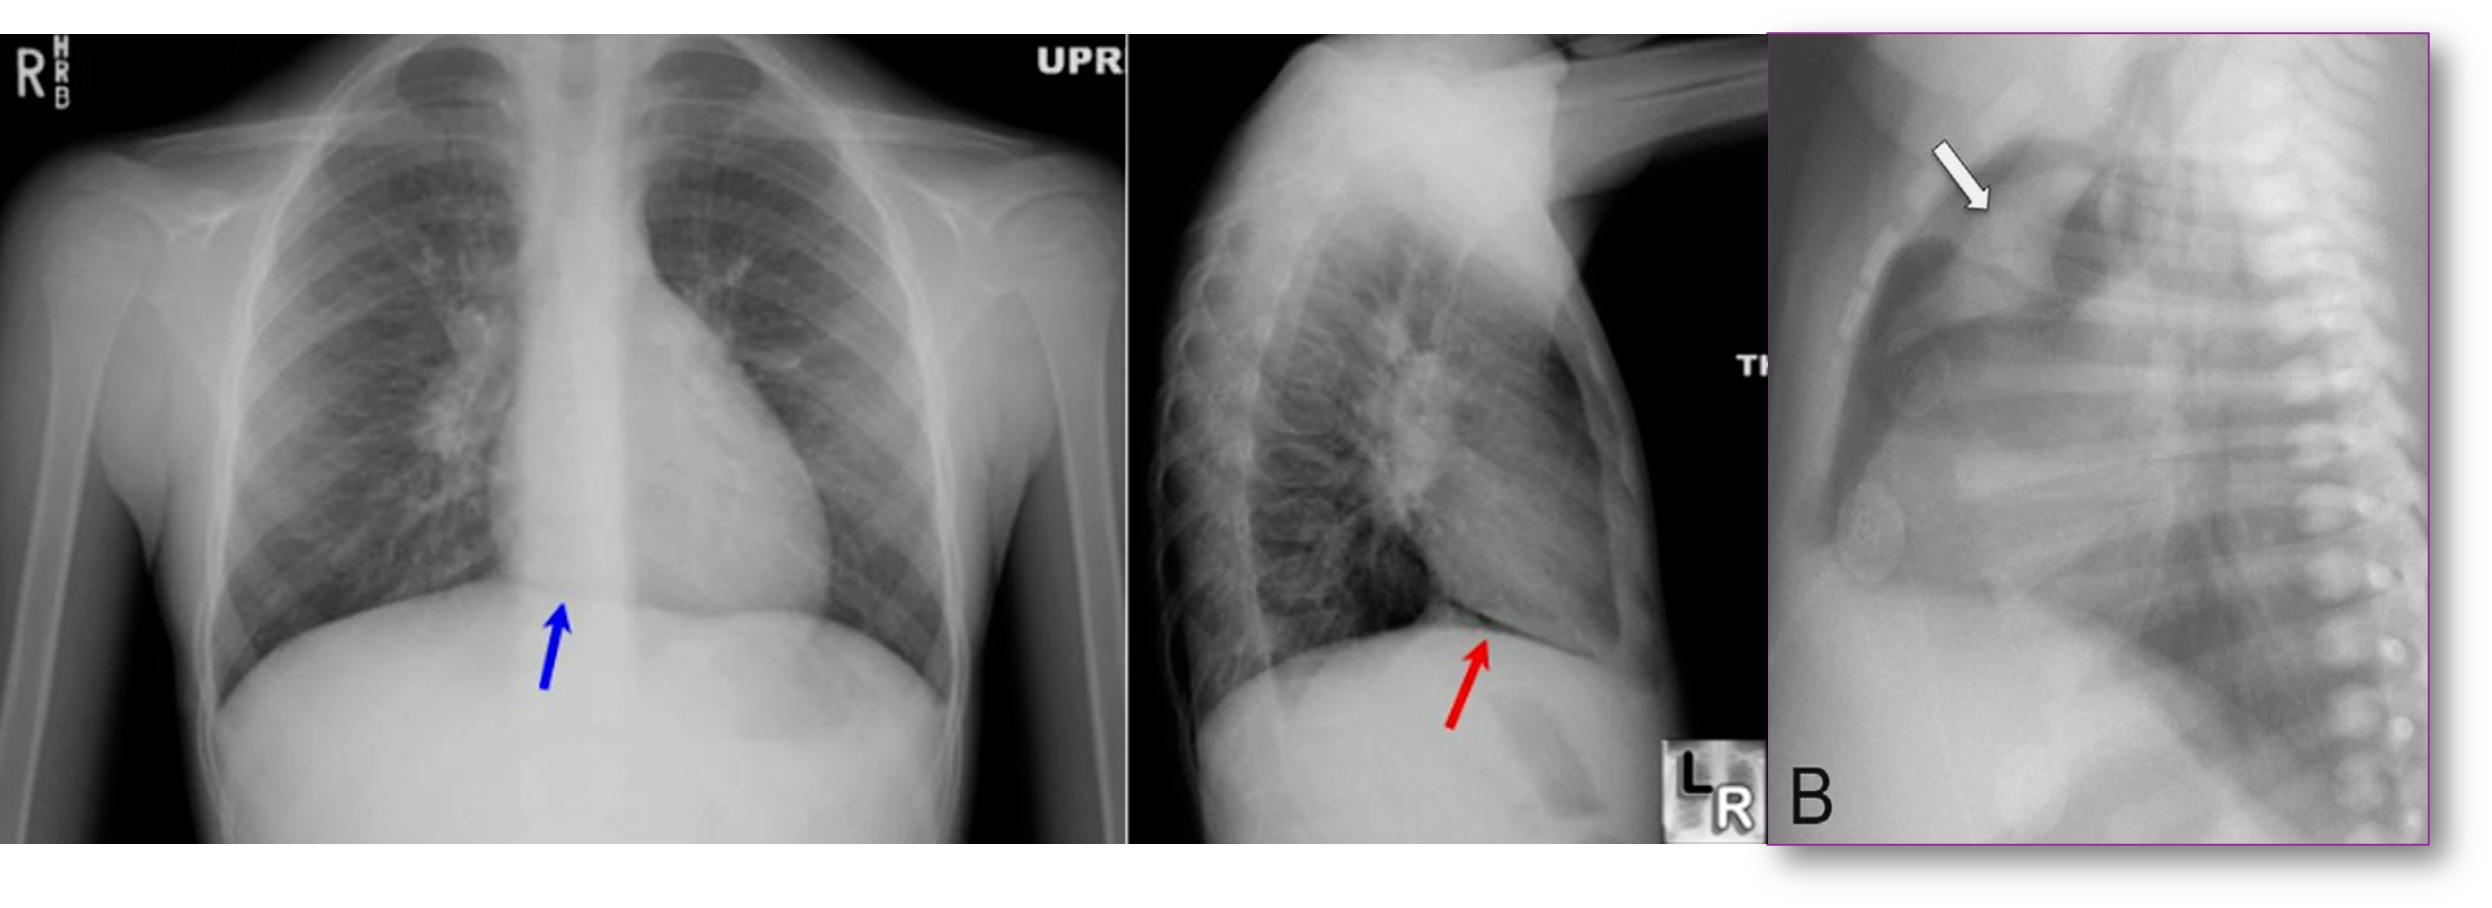

Continuous Diaphragm Sign

- Description:

The blue arrow points to the “continuous diaphragm sign.” The entire diaphragm is visualized from one side to the other because air in the mediastinum outlines the central portion, which is usually obscured by the heart and mediastinal soft tissue structures that are in contact with the diaphragm. The red arrow points to the air beneath and posterior to the heart. Pneumomediastinum elevating the thymus causing the “spinnaker sail” sign. Notice also the “continuous diaphragm line.”